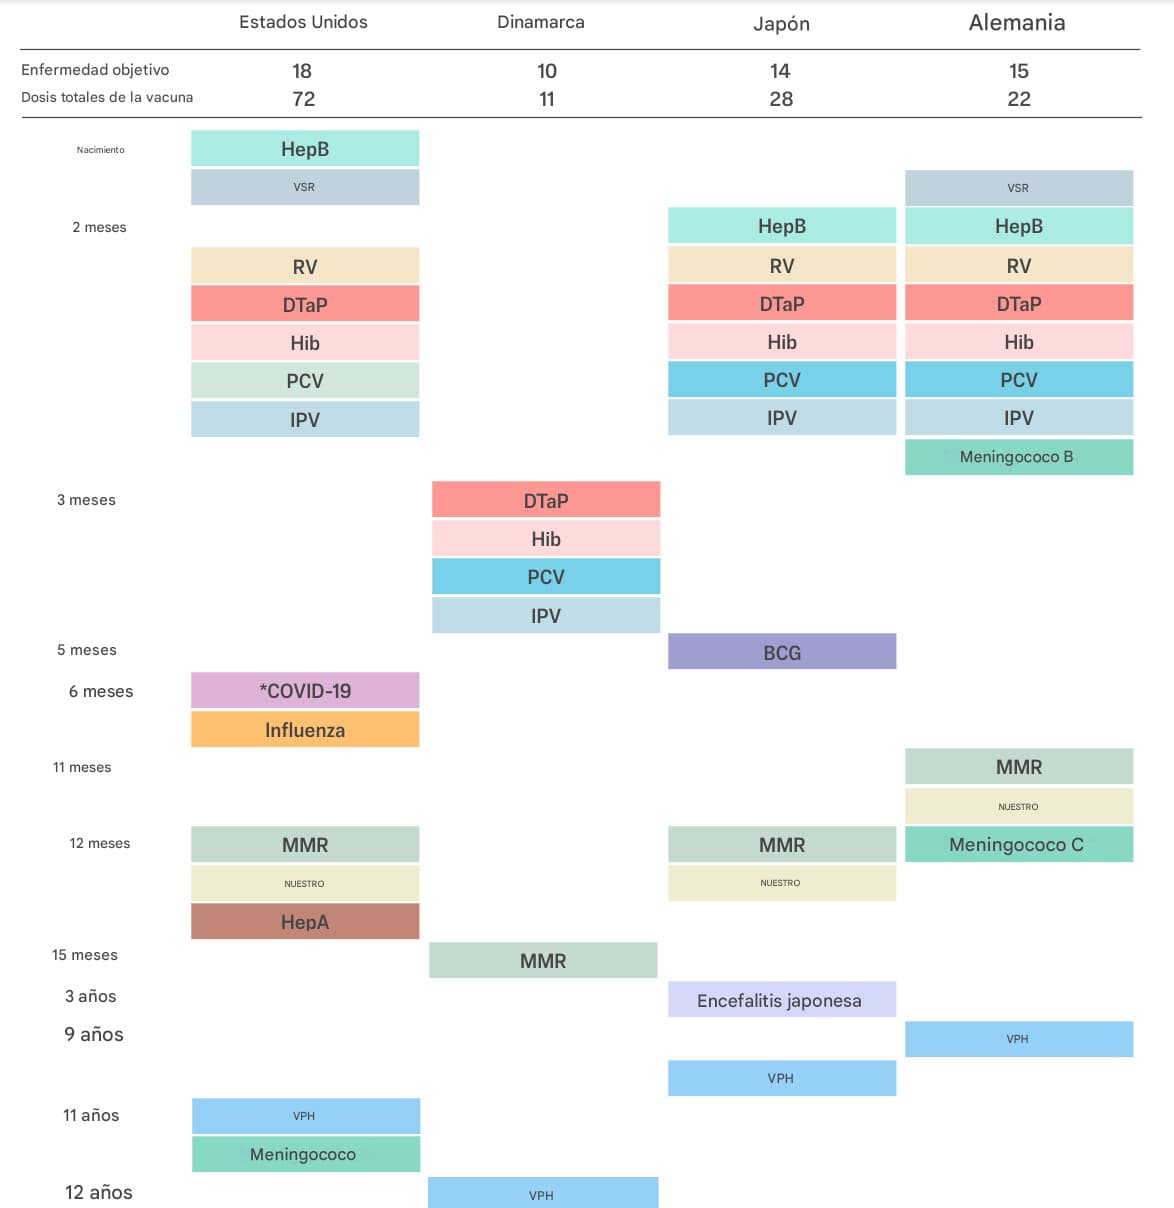

Cómo podría cambiar el calendario de vacunación infantil bajo la directiva de Trump